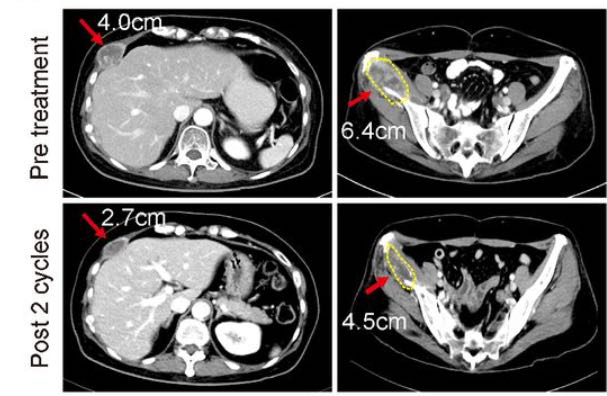

- 乳腺癌治疗

:针对HER2阳性的实体瘤(主要为乳腺癌),NK细胞疗法联合曲妥珠单抗的I期临床试验结果显示,1例既往接受过多种治疗均失败的乳腺癌患者,在输注NK细胞两个周期后,肿瘤实现了部分缓解。